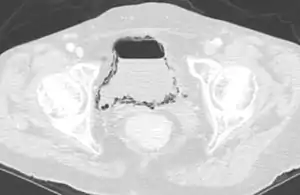

| Emphysematous cystitis in computertomography | |

- A gas-producing UTI (emphysematous cystitis: rare).

Diagnosis is made by patient history of passing air or a sputtering urine stream. CT scans may show air in the urinary bladder or bladder walls.